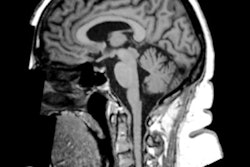

On the fifth day, the subjects underwent fMRI scans, which revealed increased activity in the right insula region of the brain when they drank the real walnut smoothie compared with the fake drink. The insula is associated with cognitive control and salience, which would indicate that the smoothie consumers were paying more attention to food choices and selecting the less desirable or healthier options over the highly desirable or less healthy options.